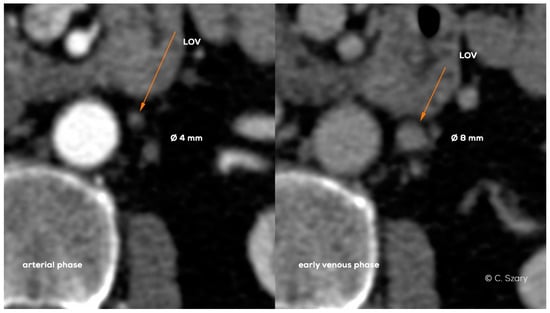

- the mean diameter of ovarian veins (the upper and lower segments are always assessed in the late phase of contrast enhancement);

- −

- the rate and order of the ovarian veins contrasting;

- the dynamics of contrast enhancement in ovarian and iliac veins, assessed in dynamic radiological sequences;